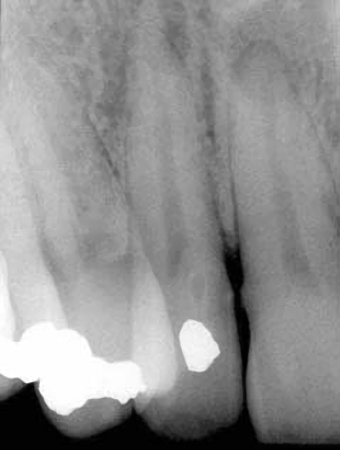

Que entidad patológica esta presente en esta imagen radiográfica ?